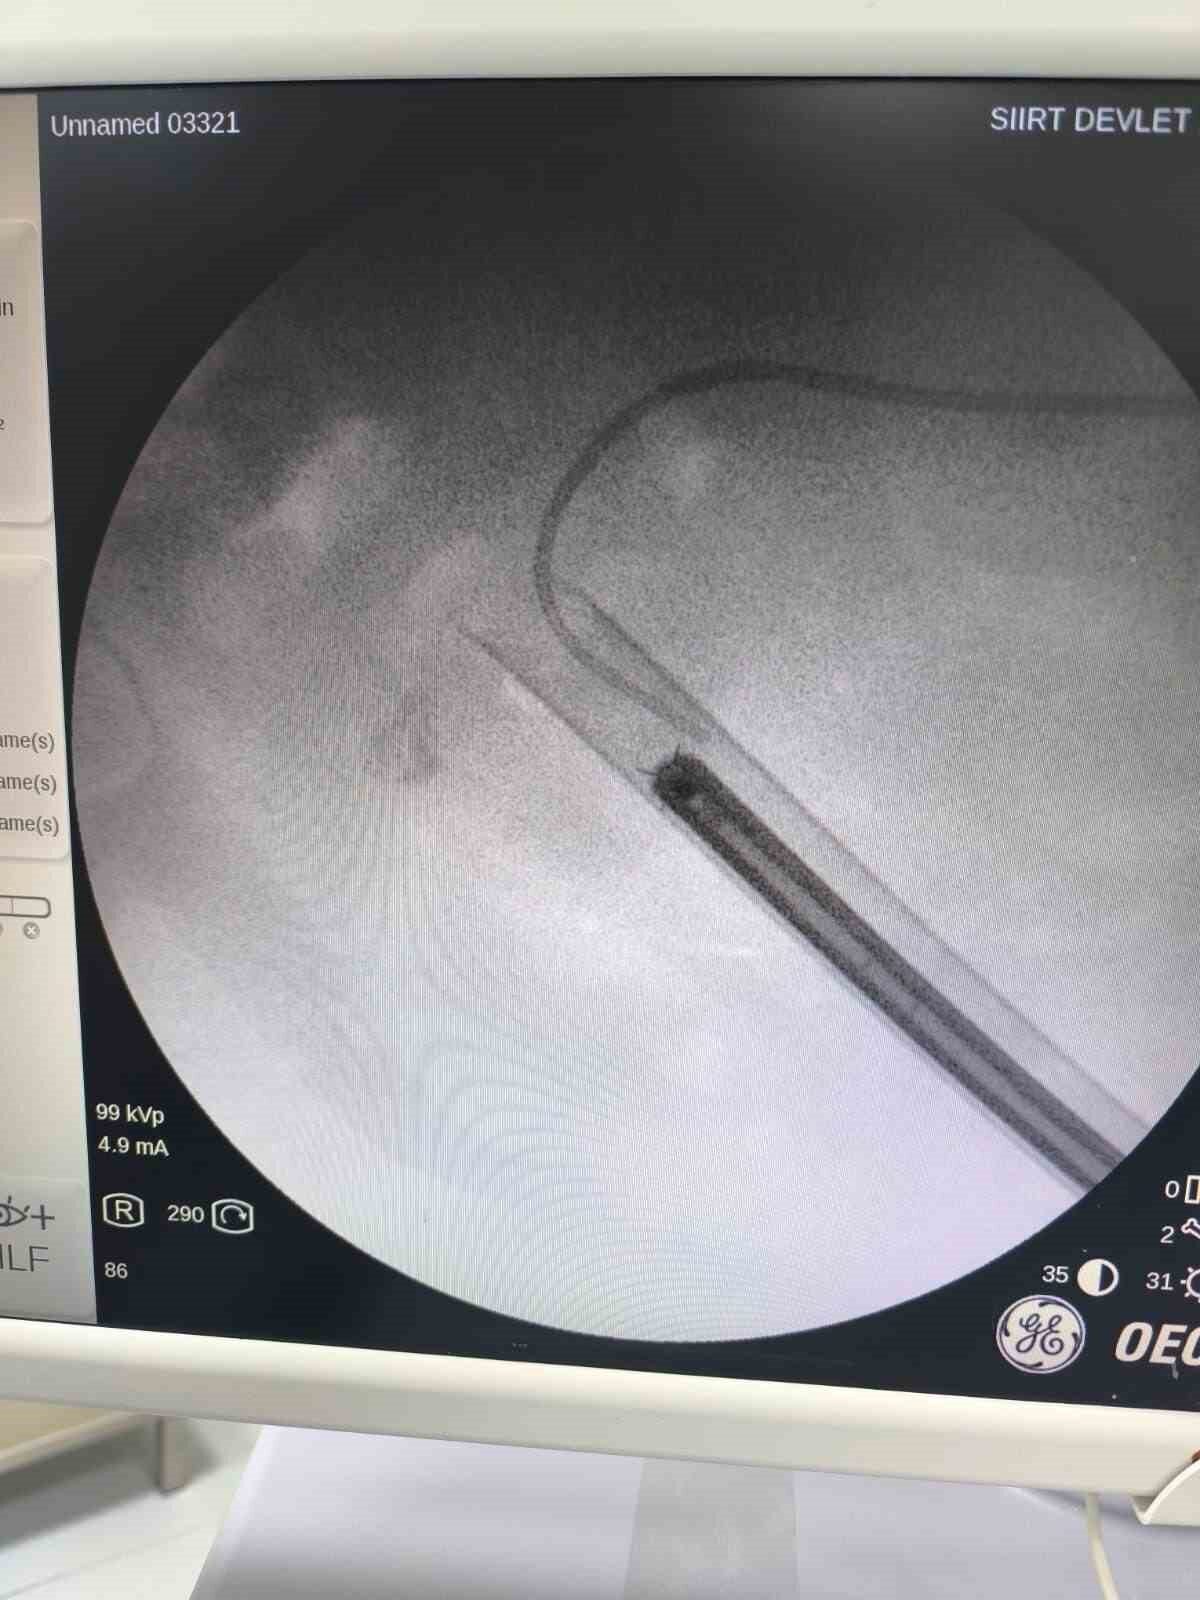

Siirt’te 34 yaşındaki Fatih Aslan, ateş, üşüme ve idrar yaparken yanma şikayetleriyle hastaneye başvurdu. Yapılan muayene ve testlerin ardından piyelonefrit (böbrek iltihabı) tanısı konuldu ve enfeksiyon tedavisi başarıyla tamamlandı. Üroloji uzmanı doktor Miraç Ataman, gerçekleştirilen operasyonun hem tıbbi açıdan hem de toplumsal sağlık açısından önemli bir başarı olduğunu ifade etti. Ataman, “34 yaşındaki erkek hastamız, ateş, üşüme ve idrar yaparken yanma şikayetleri ile acil servise başvurdu. Yapılan değerlendirme sonunda piyelonefrit (böbrek iltihabı) tanısı konuldu ve yatağa alınarak enfeksiyon tedavisi başarıyla tamamlandı. Tanı sürecinde yapılan Bilgisayarlı Tomografi (BT) görüntülemesinde böbreğin tamamını kaplayan, sert yapıda (950-1450 HU), literatürde staghorn olarak adlandırılan ve halk arasında ‘geyik boynuzu taşı’ olarak bilinen büyük taş tespit edildi. Staghorn taşlar, böbreğin tüm boşluklarını doldurduğundan, tekrarlayan enfeksiyonlara ve uzun vadede böbrek fonksiyon kaybına yol açabilmektedir. Bu sebeple tedavisi hayati önem taşımaktadır. Biz de bu vakamızda, Perkütan Nefrolitotomi (PCNL) yöntemiyle böbreğe küçük bir cilt kesisi üzerinden girerek endoskopik cihazlarla taşları parçalayıp çıkardık. PCNL, özellikle çapı 2 cm’den büyük ve karmaşık taşlarda altın standart olarak kabul edilmektedir. Normalde staghorn taşların temizlenmesi uzun süren ve çoğu zaman birden fazla seans gerektiren zorlu bir süreçtir. Modern altyapısı sayesinde, ciltten tek bir giriş yolu açılarak yaklaşık 1,5 saatlik bir seansta böbreğin tüm taş yükü başarıyla temizlendi” dedi.